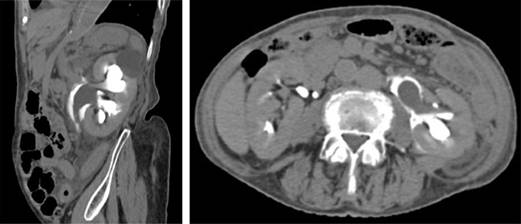

Figura 2: Fase tardía de tomografía de abdomen con contraste intravenoso donde se observa extravasación de orina con medio de contraste a nivel de la pelvis renal.

Las fugas de orina o urinomas pueden estar ocultas inicialmente y pueden dar lugar a complicaciones, como la formación de abscesos y desequilibrios electrolíticos, si no se diagnostican de inmediato y se manejan adecuadamente. La tomografía computarizada con medio de contraste intravenoso es el estudio de elección en el diagnóstico de fugas de orina y urinomas renales. Los protocolos de tomografía en pacientes con sospecha de pérdida de orina implican escanear el abdomen antes y después de la administración intravenosa de 100-150 mL de material de contraste. Las imágenes de fase retrasada (obtenidas de cinco a 20 minutos después de la inyección de material del contraste) son la clave para demostrar una fuga de orina, porque la orina yodada aumenta la atenuación del urinoma con el tiempo. Las imágenes de tomografía reformateadas en reconstrucciones coronales y sagitales pueden ayudar a definir aún más el alcance de las lesiones en el sistema colector.

Incluso si no se sospecha de una fuga de orina renal o de un urinoma en el momento en que se prescribe el protocolo de la tomografía, todavía se puede diagnosticar después de la adquisición si se reconoce la ubicación y el patrón de diseminación de la colección de líquido. Los urinomas pueden ser confinados como colecciones de líquido encapsuladas o pueden manifestarse como líquido libre. Sin embargo, la mayoría de los urinomas se filtran a una ubicación subcapsular o al espacio perirrenal dentro de la fascia de Gerota. Si es extensa la fuga de orina puede llegar a la aorta y a la vena cava inferior y, de ahí, extenderse hacia el espacio perirrenal contralateral.